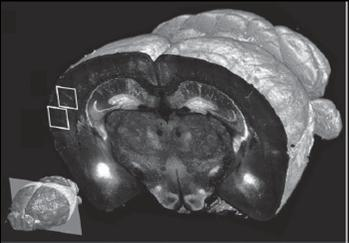

One set of experiments tested the technology at different levels of resolution. At 10x magnification of brain tissue samples, they performed fast imaging "at a resolution sufficient to visualize the distribution and morphology of green-fluorescent protein-labeled neurons, including their dendrites and axons," reports Osten.

The team was able to obtain a full set of data, including final images, in 6.5 to 8.5 hours per brain, depending on the resolution. These sets each were comprised of 260 top-to-bottom, or coronal, slices of mouse brain tissue, which were assembled by computer into three-dimensional (3-D) renderings themselves capable of a wide range of "warping"âi.e., artificial manipulationâto reveal hidden structures and features.